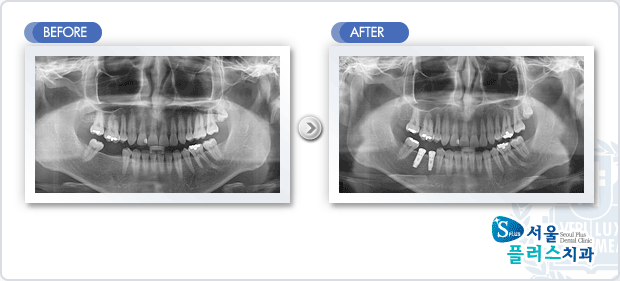

[임플란트] 임플란트 - 하악 구치부 상실부위 임플란트 식립